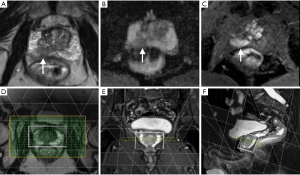

For each patient, at least 6–8 weeks were allowed to elapse between the latest intra-prostatic biopsies and the mp-MRI imaging. All imaging was performed using a specific protocol that included T1-, T2-, diffusion-, and perfusion-weighted imaging as well as multi-voxel spectroscopy sequences on a 3.0T Trio Trim Siemens (Erlangen, Germany) unit with a phased-array torso coil and no endorectal coil (Figure 1). The standard MRI protocol and acquisition parameters used were as follows:

- Spectroscopic imaging: after application of saturation bands excluding the peri-prostatic tissue, rectum, and seminal vesicles, thus defining the acquisition volume of the spectra, we obtained a matrix with 16 slices, 16 lines, and 16 columns, with a 3D FOV that provided a spectral resolution of about 0.14 cm3. The spectra were sampled at 512 points with a 1,250-Hz bandwidth (or 1,250 Hz/123.218 MHz ≈10.14 ppm). The NMR-S sequence acquisition time was 10 minutes with TR =720 ms and TE =140 ms; additional spectroscopic sequences without water suppression (1.5 minutes) were acquired with the same TR values but with different TE values (30, 80, and 140 ms) to allow intra-prostatic water characterization in T2, in order to normalize the metabolites based on the water peak. A 3D Shim was systematically performed for verification of the magnetic field homogeneity and on measurement of the full width at half maximum (FWHM) of the water peak before the first acquisition: we observed a 20–30 Hz value within the whole volume of interest and 8–13 Hz for each voxel (Figure 2);